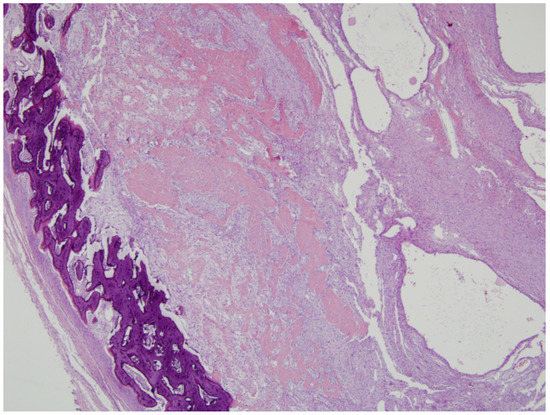

Chest X-ray images showed a radiopaque mass with rim calcification at the T4/5 paraspinal area (Figure 2). Computed tomography images revealed an approximately 2.8 × 2.5 cm wide, 4.5 cm high oval-shaped mass in the right paraspinal muscle with peripheral rim calcification (Figure 2) that was not seen on computed tomography images 5 months prior. The cleft between the mass and the adjacent bone was visible. On magnetic resonance imaging (MRI), the mass showed a heterogeneous high signal intensity on T2WI, isointense to muscle on T1WI with a peripheral low signal intensity rim, and homogeneous enhancement. In addition, perilesional soft tissue edema at the adjacent muscle was also noted (Figure 3). With a history of suspicious trauma (extracorporeal shock wave therapy) and radiologic findings, myositis ossificans was the most suspected diagnosis.

Figure 5. Histologic findings of biopsy (H&E stain). (a) On scanning view (×25), the biopsied tissue had two components, including a hypercellular area (left portion of the tissue, red-colored circle) and highly sclerotic area (right portion, blue-colored circle). (b) The cellular area showed ovoid to spindle-shaped cellular proliferation in edematous background. Additionally, there were extravasated erythrocytes, and the stroma had increased vascularity (×200). (c) The area, which was observed as hypersclerotic on scanning view, showed woven bone formation (arrows) and had mineralization (empty arrow) (×200). (d) The central area had a transition of the hypercellular component with woven bone formation (×40). Overall, the histologic findings were compatible with MO.